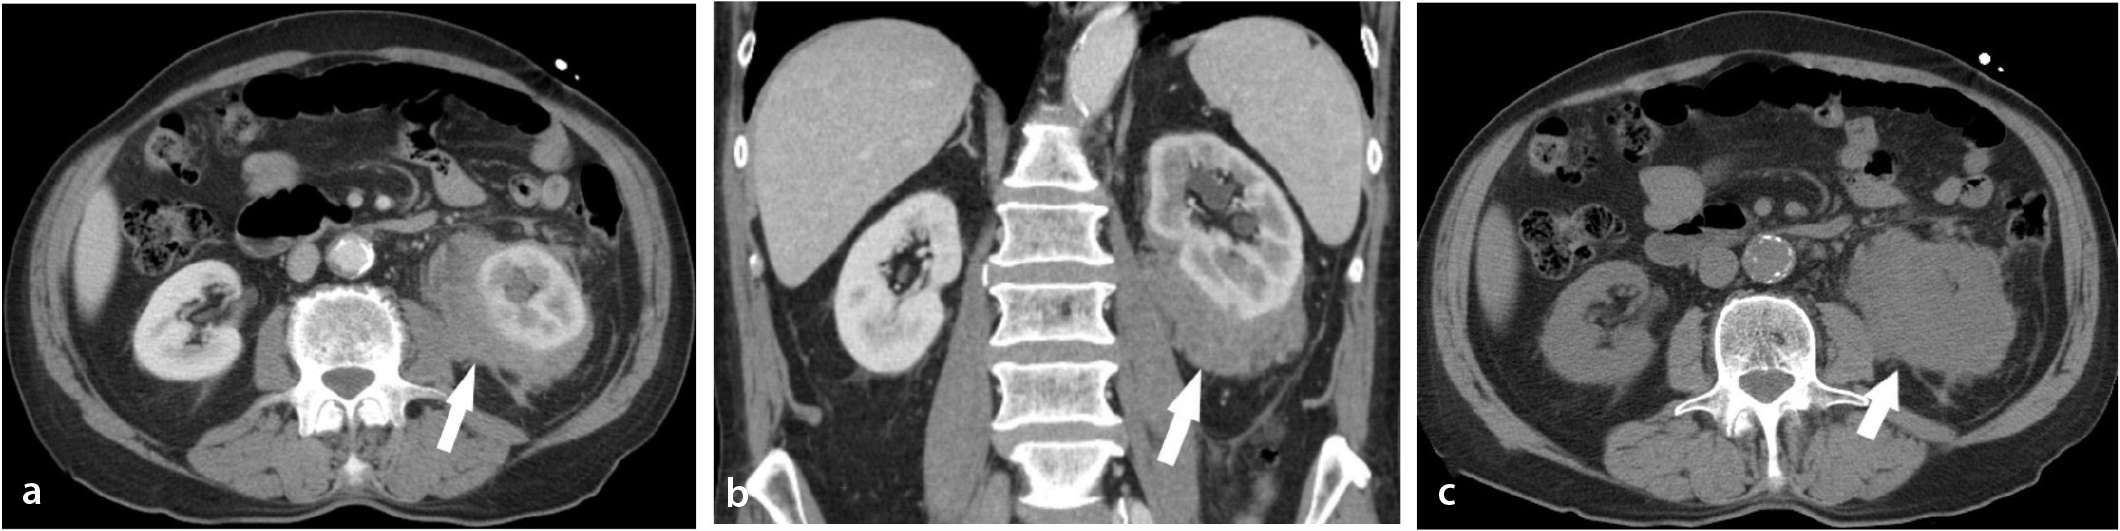

A 30-year-old woman presents to her primary care provider with blood in her urine and pain in her left flank. She has a 5-year history of polycystic ovarian syndrome managed with oral contraceptives and metformin. She is single and is not sexually active and denies a history of kidney stones or abdominal trauma. She has a 15-pack-year smoking history but denies the use of other substances. Her family history is significant for fatal lung cancer in her father at age 50, who also smoked, and recently diagnosed bladder cancer in her 45-year-old brother, who never smoked. On review of systems, she denies weight loss, fever, fatigue, paresthesia, increased pain with urination, or excessive bleeding or easy bruising. She is admitted to the hospital for a workup and observation. Her vital signs and physical exam are within normal limits. A urine pregnancy test is negative. PT is 14 sec and PTT is 20 sec. The rest of the laboratory results including von Willebrand factor activity and lupus anticoagulant panel are pending. A CT angiogram is ordered and is shown in the picture. What is indicated at this time to prevent a potential sequela of this patient’s condition?